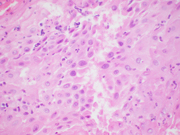

Figure 1. Cervical Pap test, ThinPrep, Papanicolaou stain, 400X magnification

On the ThinPrep, the cells are mostly seen in clusters or lying singly. They are large cells with well-defined moderate to abundant amounts of granular to vacuolated cytoplasm. The nuclear:cytoplasmic (N:C) ratio is variable and is focally increased. The nuclei are round to ovoid. The chromatin is mostly granular, the nuclear membranes are smooth to mildly irregular, and the nucleoli are prominent (Images 1-3). On the cell block section, decidua is seen in the form of flat sheets with round to polygonal epithelioid cells with well-defined eosinophilic cytoplasm. The nuclear characteristics are similar to that noted on the ThinPrep except that the chromatin is vesicular to granular (probably related to the differences in the stain) (Images 4-6).

The decidua cells can be easily misinterpreted as a significant squamous cell or glandular cell abnormality on cytology, owing to the overlap in their cytomorphology. ASC-H and HSIL cells, however, tend to show denser cytoplasm, coarser chromatin, more uniformly higher N:C ratios and pronounced nuclear membrane irregularities, and less apparent nucleoli. Atypical glandular cells of endocervical origin, unless originating from a higher grade adenocarcinoma, are typically more columnar with mild to moderate crowding and stratified, elongated hyperchromatic nuclei. Atypical glandular cells of endometrial origin usually exhibit more crowded three-dimensional groups with enlarged nuclei, granular to vesicular chromatin and prominent nucleoli.